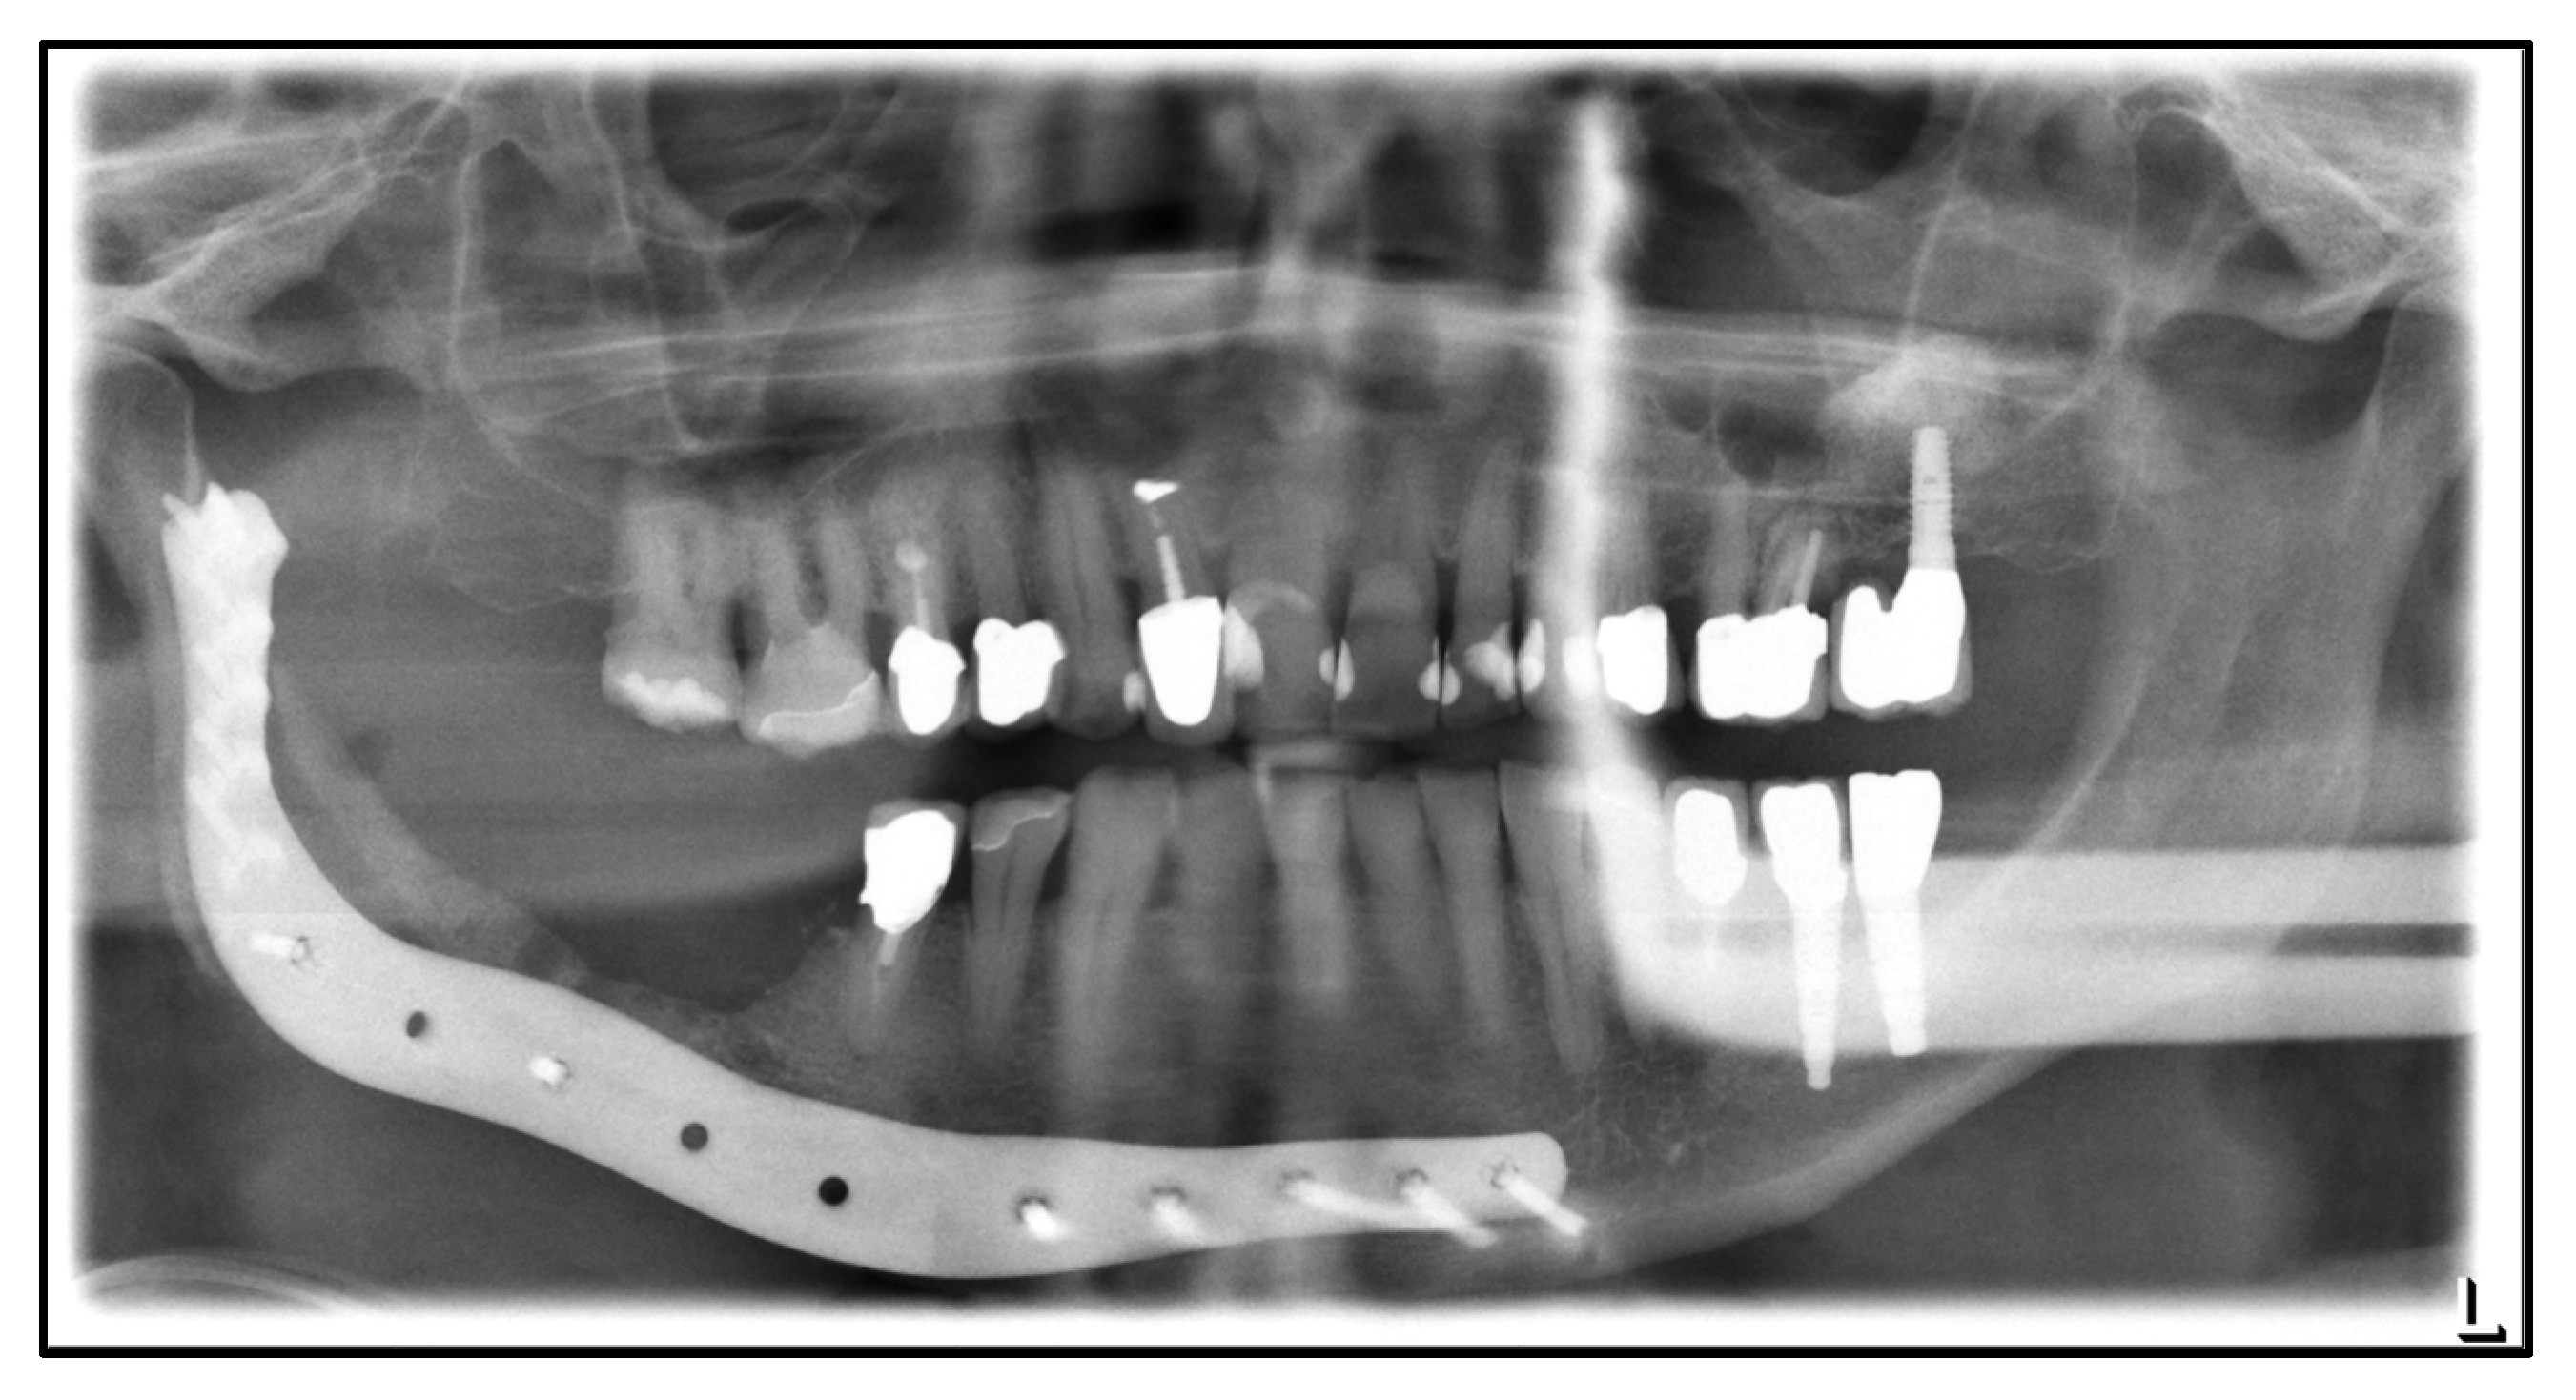

| July 2014: | Diagnosis of MRONJ in the right molar region of the mandible. Following mandibular box resection and protective plate osteosynthesis with a patient-specific plate. |

| August 2018: | Partial mandibular resection with continuity defect and alloplastic reconstruction using a patient-specific plate, excision of a submental fistula |

| November 2018: | Cervical abscess on the right side with infected osteosynthesis material. Decortication and partial removal of the PSI. |

| September 2022: | Partial mandibular resection from the left mandibular angle to the right mandible, including the right temporomandibular joint, CAD/CAM-guided reconstruction with a bilateral free scapula flap with skin island, and patient-specific plate. In the course: